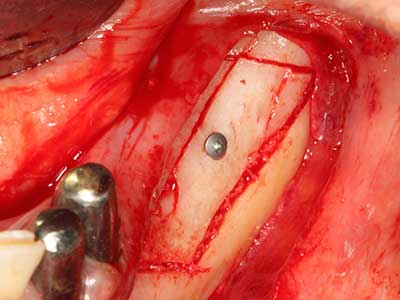

Пиезохирургията има допълнителни предимства при събиране на костни блокове. В допълнение към високата прецизност при остеотомията, описана по-горе, употребата на фините режещи накрайници значително намаляват загубата на материал. Голяма загуба на материал по време на събиране може да се очаква с дебелите накрайници, особено при употреба на борери Линдеман (Lakshmiganthan, Gokulanathan et al. 2012). Базалното разделяне, което е необходимо, особено за присадка на блок при ретромолар, е улеснено от специално създадени правоъгълни триони. В резултат на това, пиезохирургията е разглеждана като прецизна, улеснена и безопасна процедура за събиране на костни блокове в ретромоларното пространство (Happe 2007) (Фиг. 1-12).